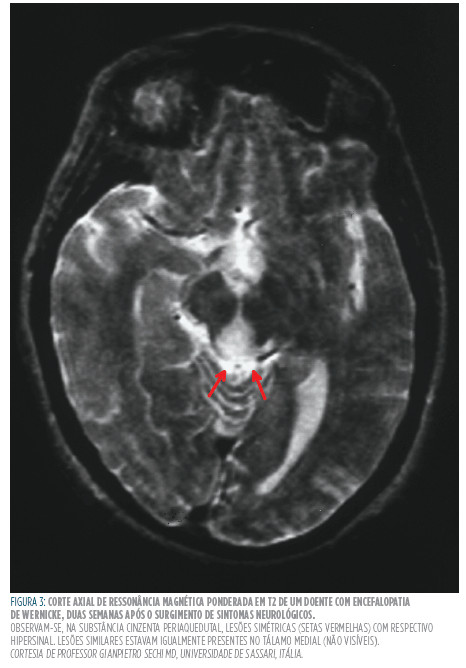

Como já for referido anteriormente, o subdiagnóstico desta patologia pode ser parcialmente explicado tanto pela variabilidade de apresentações clínicas como também devido à baixa especificidade dos sinais neurológicos.33,34 na fase aguda de deficiência em tiamina, os sintomas e sinais apresentados são vagos, podendo existir envolvimento neurológico (anormalidades oculares, estado mental alterado, estupor, crises epilépticas, halucinações) e cardiovasculares (hipotensão etaquicardia, insuficiência cardíaca). Já numa fase crónica, estes são mais específicos existindo confabulações e uma perda marcada da memória anterógrada comparativamente às restantes capacidades cognitivas.28 O seu diagnóstico é essencialmente clínico uma vez que não existem exames de rotina específicos que possibilitam a sua despistagem.28,34 Sendo assim, o clínico deve suspeitar a presença do síndrome em indivíduos que se apresentem malnutridos ou condições que amplifiquem a taxa metabólica ou interfiram com os processos de ingestão, digestão e absorção dos alimentos.35 O diagnóstico pode ser feito ao determinar a concentração sérica de tiamina, dos níveis de actividade da transcetolase nos eritrócitos, mas dada sua inexistência na maior parte dos hospitais e baixa sensibilidade e especificidade, a ressonância magnética cerebral pode ser útil para confirmar a suspeita clínica (Figura 2 ).28,38 A ressonância magnética (RM), com a sua elevada sensibilidade à presença de água no espaço intersticial, tornou possível uma melhor visualização dos sinais radiológicos da neuropatologia subjacente. Em algumas sequências, as lesões edematosas são reveladas ao observador como hipersinal, já que estas possuem um elevado teor em água. Enquanto que a sensibilidade da RM na detecção da encefalopatia é de apenas 53%, a sua especificidade é de 93%, o que permite que os seus achados sejam sugestivos da presença da patologia.35 Apesar da importância da ressonância magnética no diagnóstico do síndrome, os locais da lesões e as características do sinal encontrados não são patognomónicos da encefalopatia de Wernicke, por conseguinte, outras causas de encefalopatia aguda têm de ser consideradas, tais como o síndrome de Miller-Fisher, linfoma cerebral primário, doença de Behçet e ventrículoencefalite, entre outras. Outras condições como o infarto talâmico bilateral (síndrome do topo da basilar), lesão hipocampal após paragem cardiorespiratória e tumores do terceiro ventrículo devem ser englobados no diagnóstico diferencial devido à sobreposição neuroanatómica das lesões resultantes com as da encefalopatia de Wernicke.36,37

Gostaríamos de expressar a nossa gratidão ao professor Gianpietro Sechi da Universidade de Sassari por nos ter gentilmente cedido a imagem de ressonância magnética ponderada em T2 (Figura 3) e, de igual modo, o serviço de Anatomia da Faculdade de Medicina da Universidade do Porto ao possibilitar a publicação da imagem da peça cadavérica (Figura 2).